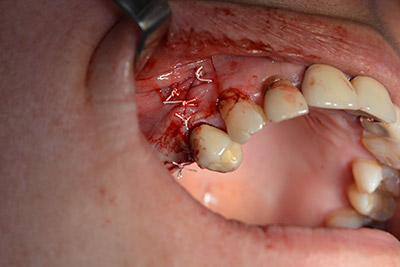

Una membrana riassorbibile viene usata come barriera in direzione buccale per contenere l'accrescimento. Infine, vengono applicate suture resistenti alla saliva (da fig. 15 a 19).